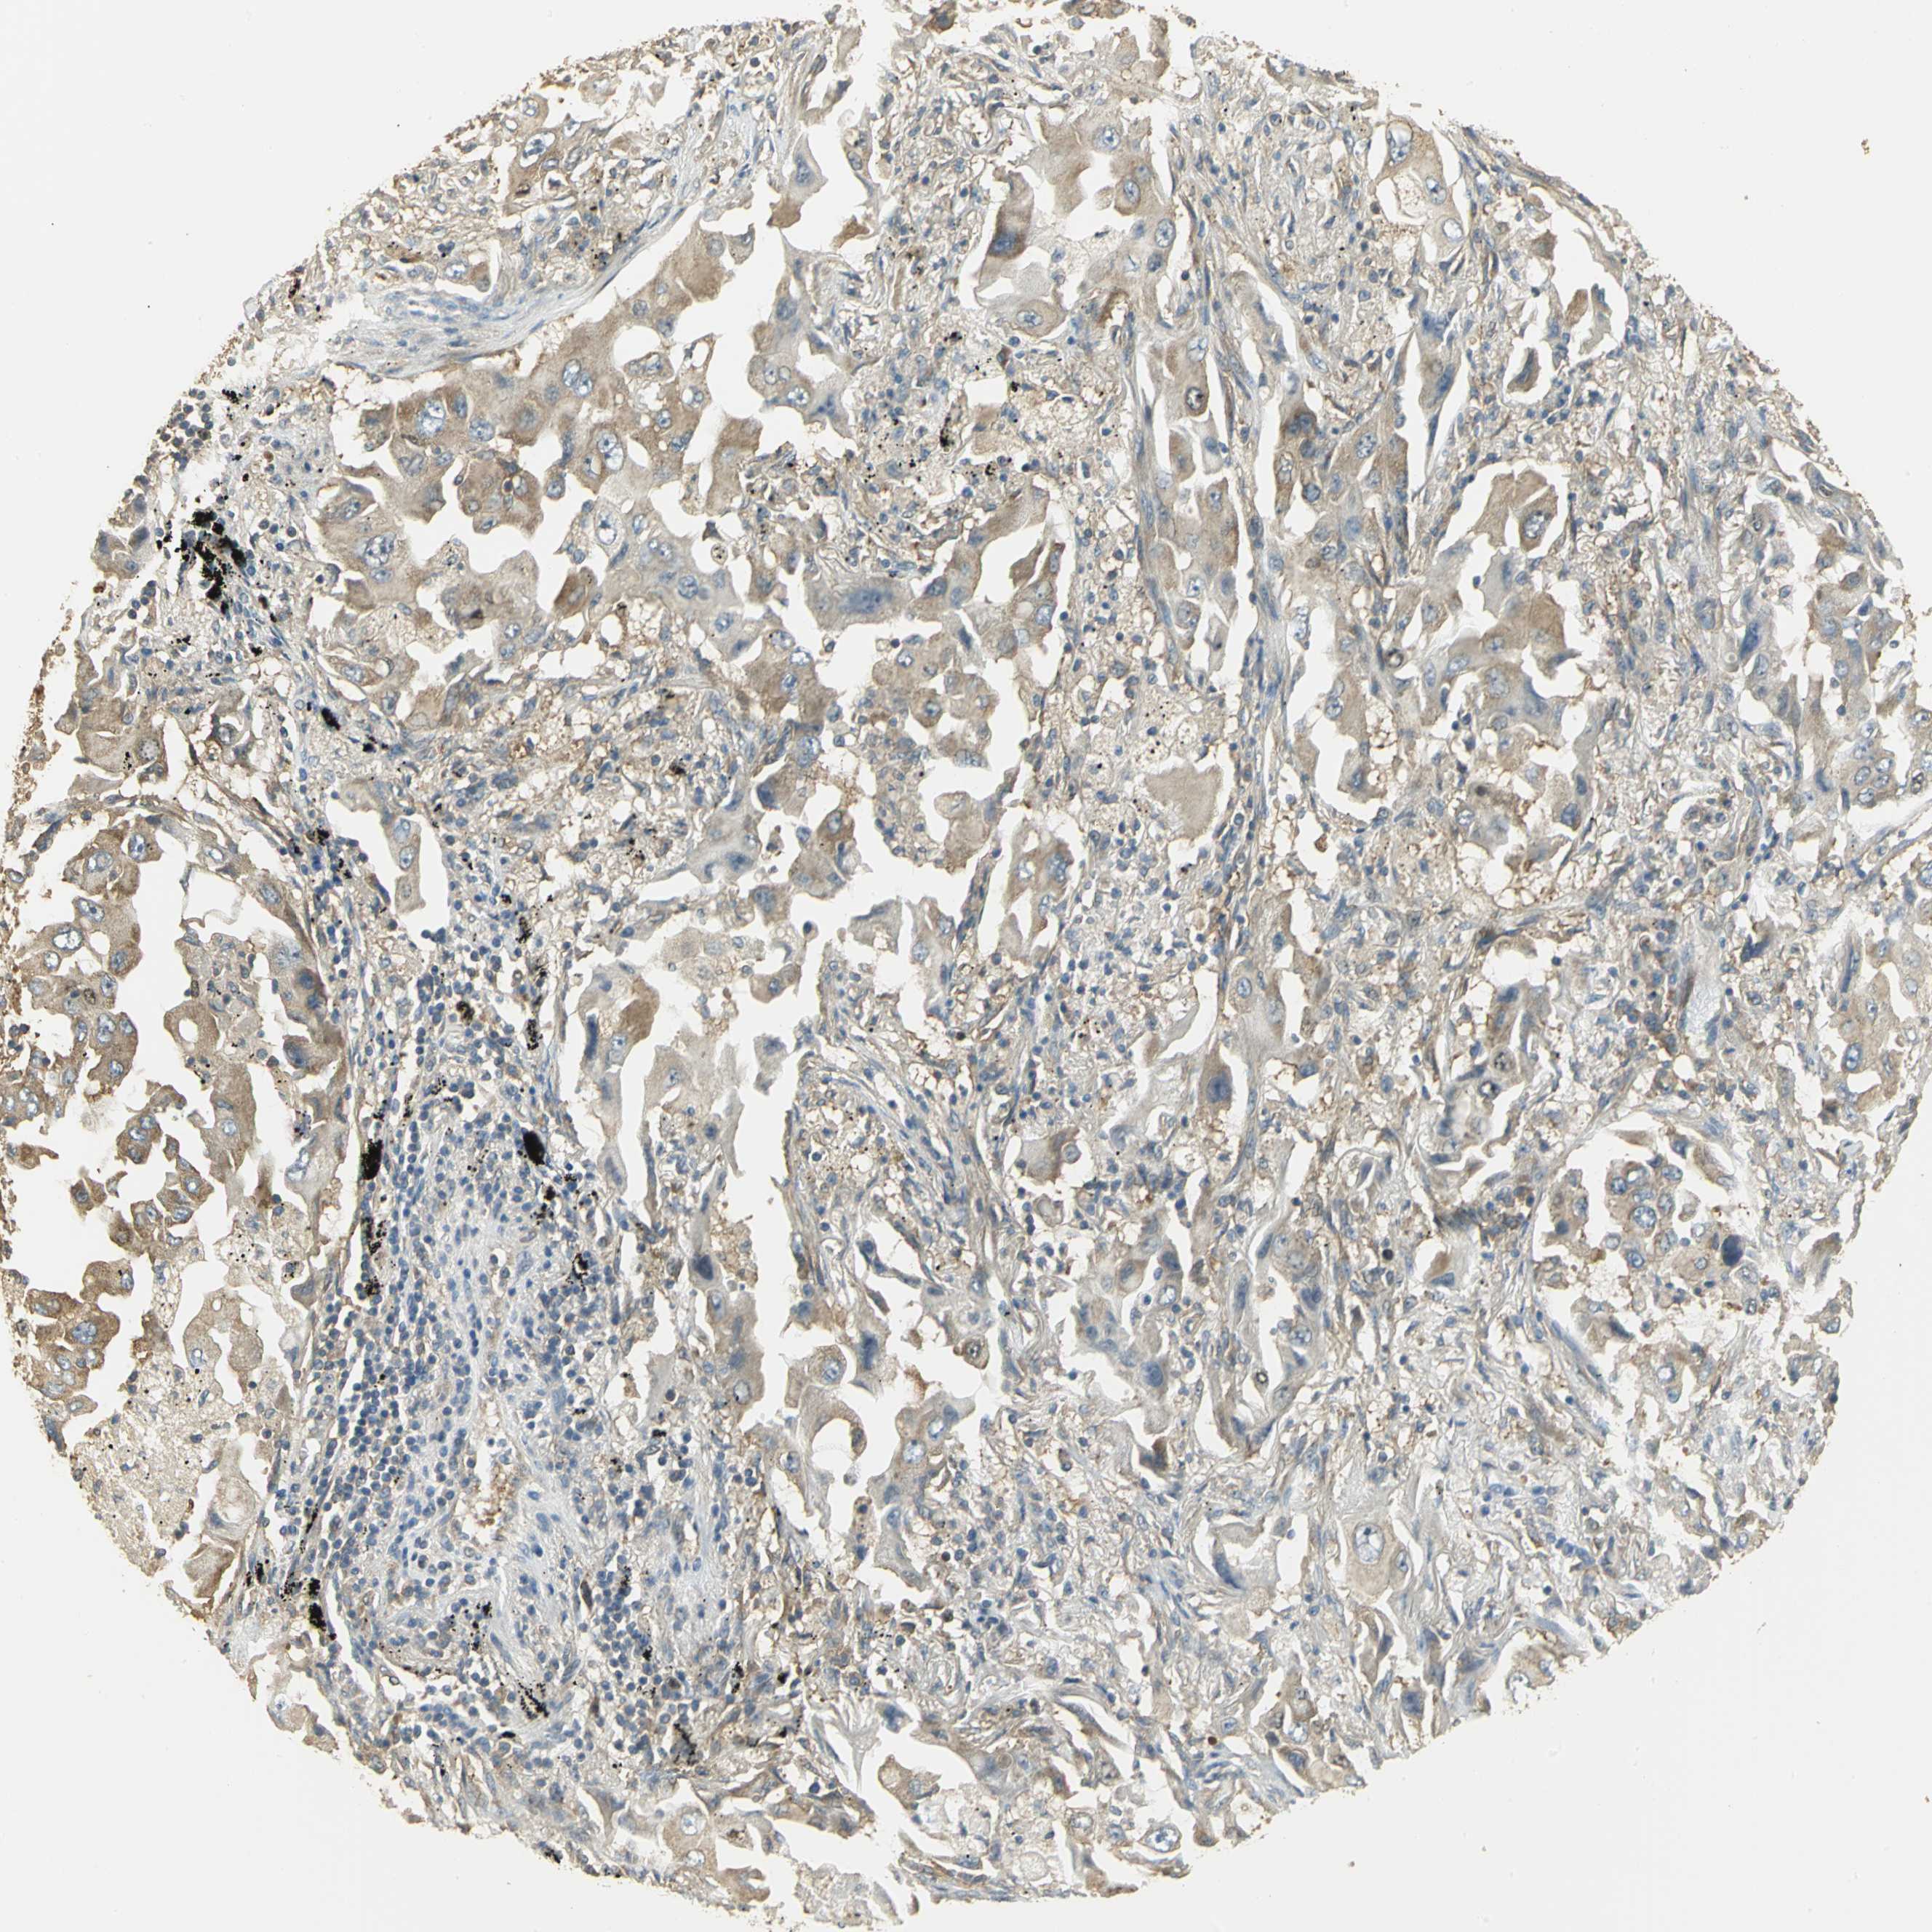

LUNG ADENOCARCINOMA (VALIDATION) - Interactive survival scatter ploti

The Survival Scatter plot shows the clinical status (i.e. dead or alive) for all individuals in the patient cohort, based on the same data that underlies the corresponding Kaplan-Meier plots. Patients that are alive at last time for follow-up are shown in blue and patients who have died during the study are shown in red.

The x-axis shows the expression levels (FPKM) of the investigated gene in the tumor tissue at the time of diagnosis. The y-axis shows the follow-up time after diagnosis (years). Both axes are complimented with kernel density curves demonstrating the data density over the axes. The top density plot shows the expression levels (FPKM) distribution among dead (red) and alive patients (blue). The right density plot shows the data density of the survived years of dead patients with high and low expression levels respectively, stratified using the cutoff indicated by the vertical dashed line through the Survival Scatter plot. This cutoff is automatically defined based on the FPKM cutoff that minimizes the p-score. The cutoff can be changed by dragging the vertical line or by entering a cutoff value in the square labeled "Current cut-off".

Under the Survival Scatter plot the p-score landscape (black curve; left axis) is shown together with dead median separation (red curve; right axis). Dead median separation is the difference in median mRNA expression between patients who have died with high and low expression, respectively. It is calculated as follows: median FPKM expression of dead patients with high expression - median FPKM expression of dead patients with low expression. This is intended to aid the user in visually exploring custom cutoffs and the associated p-scores and dead median separation.

Individual patient data is displayed and can be filtered by clicking on one or more of the category buttons on the top of the page. Categories describing expression level and patient information include: high, low, alive, dead, female, male and tumor stages. The scale of the x-axis can be toggled between linear and log-scale by clicking on the "x log" button. Mouse-over function shows TCGA ID, patient information and mRNA expression (FPKM) for each patient.

& Survival analysisi

Kaplan-Meier plots summarize results from analysis of correlation between mRNA expression level and patient survival. Patients were divided based on level of expression into one of the two groups "low" (under cut off) or "high" (over cut off). X-axis shows time for survival (years) and y-axis shows the probability of survival, where 1.0 corresponds to 100 percent.

RARS1 is not prognostic in Lung Adenocarcinoma (validation)

: 73.18

P scorei

N/A

Average pTPM 63.8

Number of samples 105